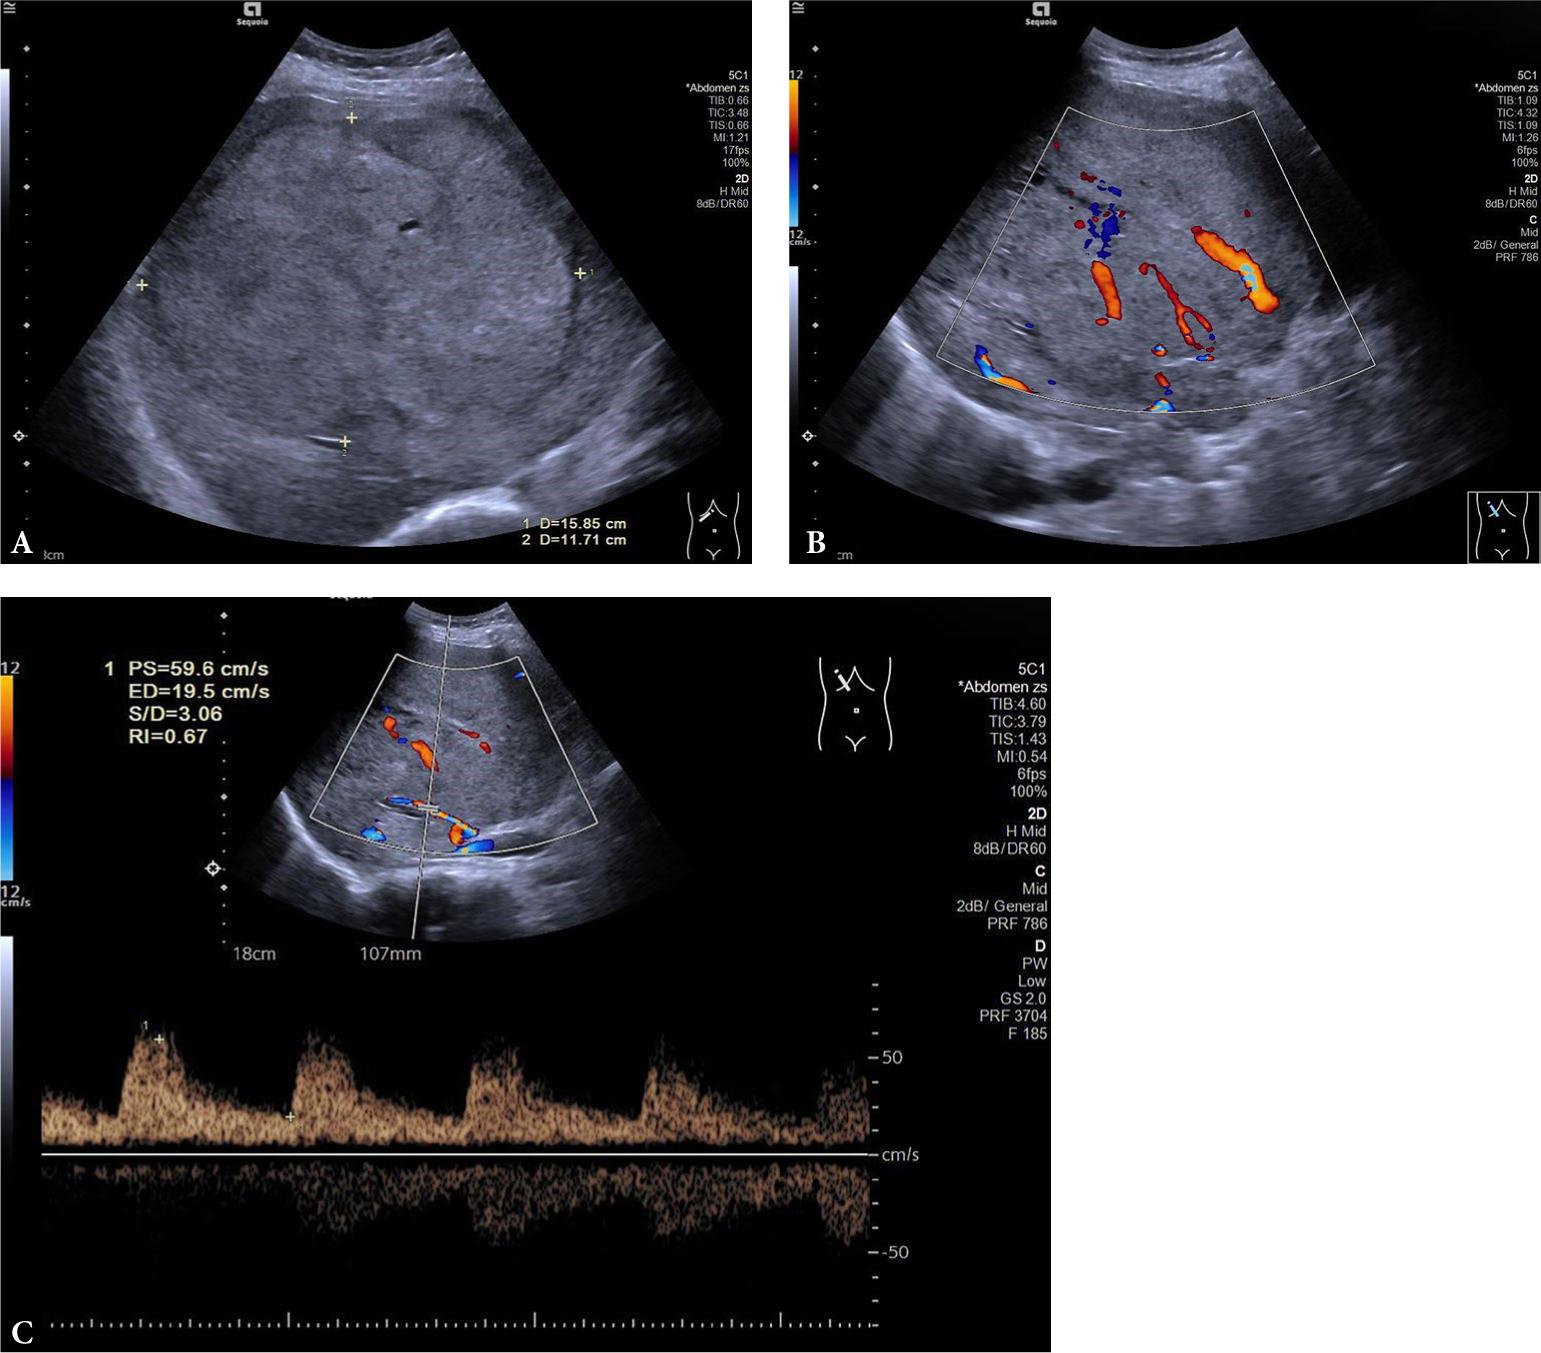

Fig. 3.